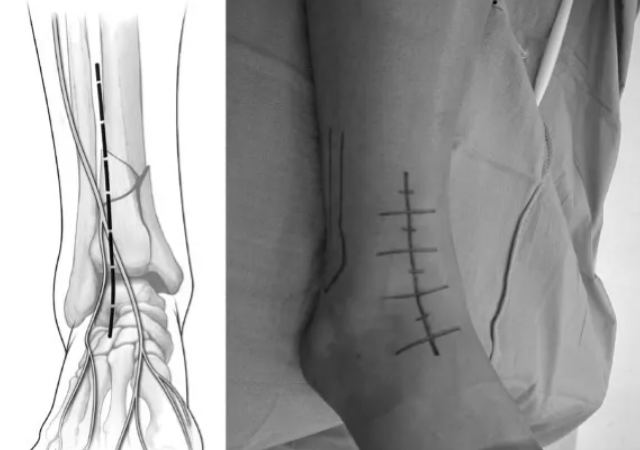

Pilon骨折常用入路详解(Harborview IllustratedTips and Tricks )